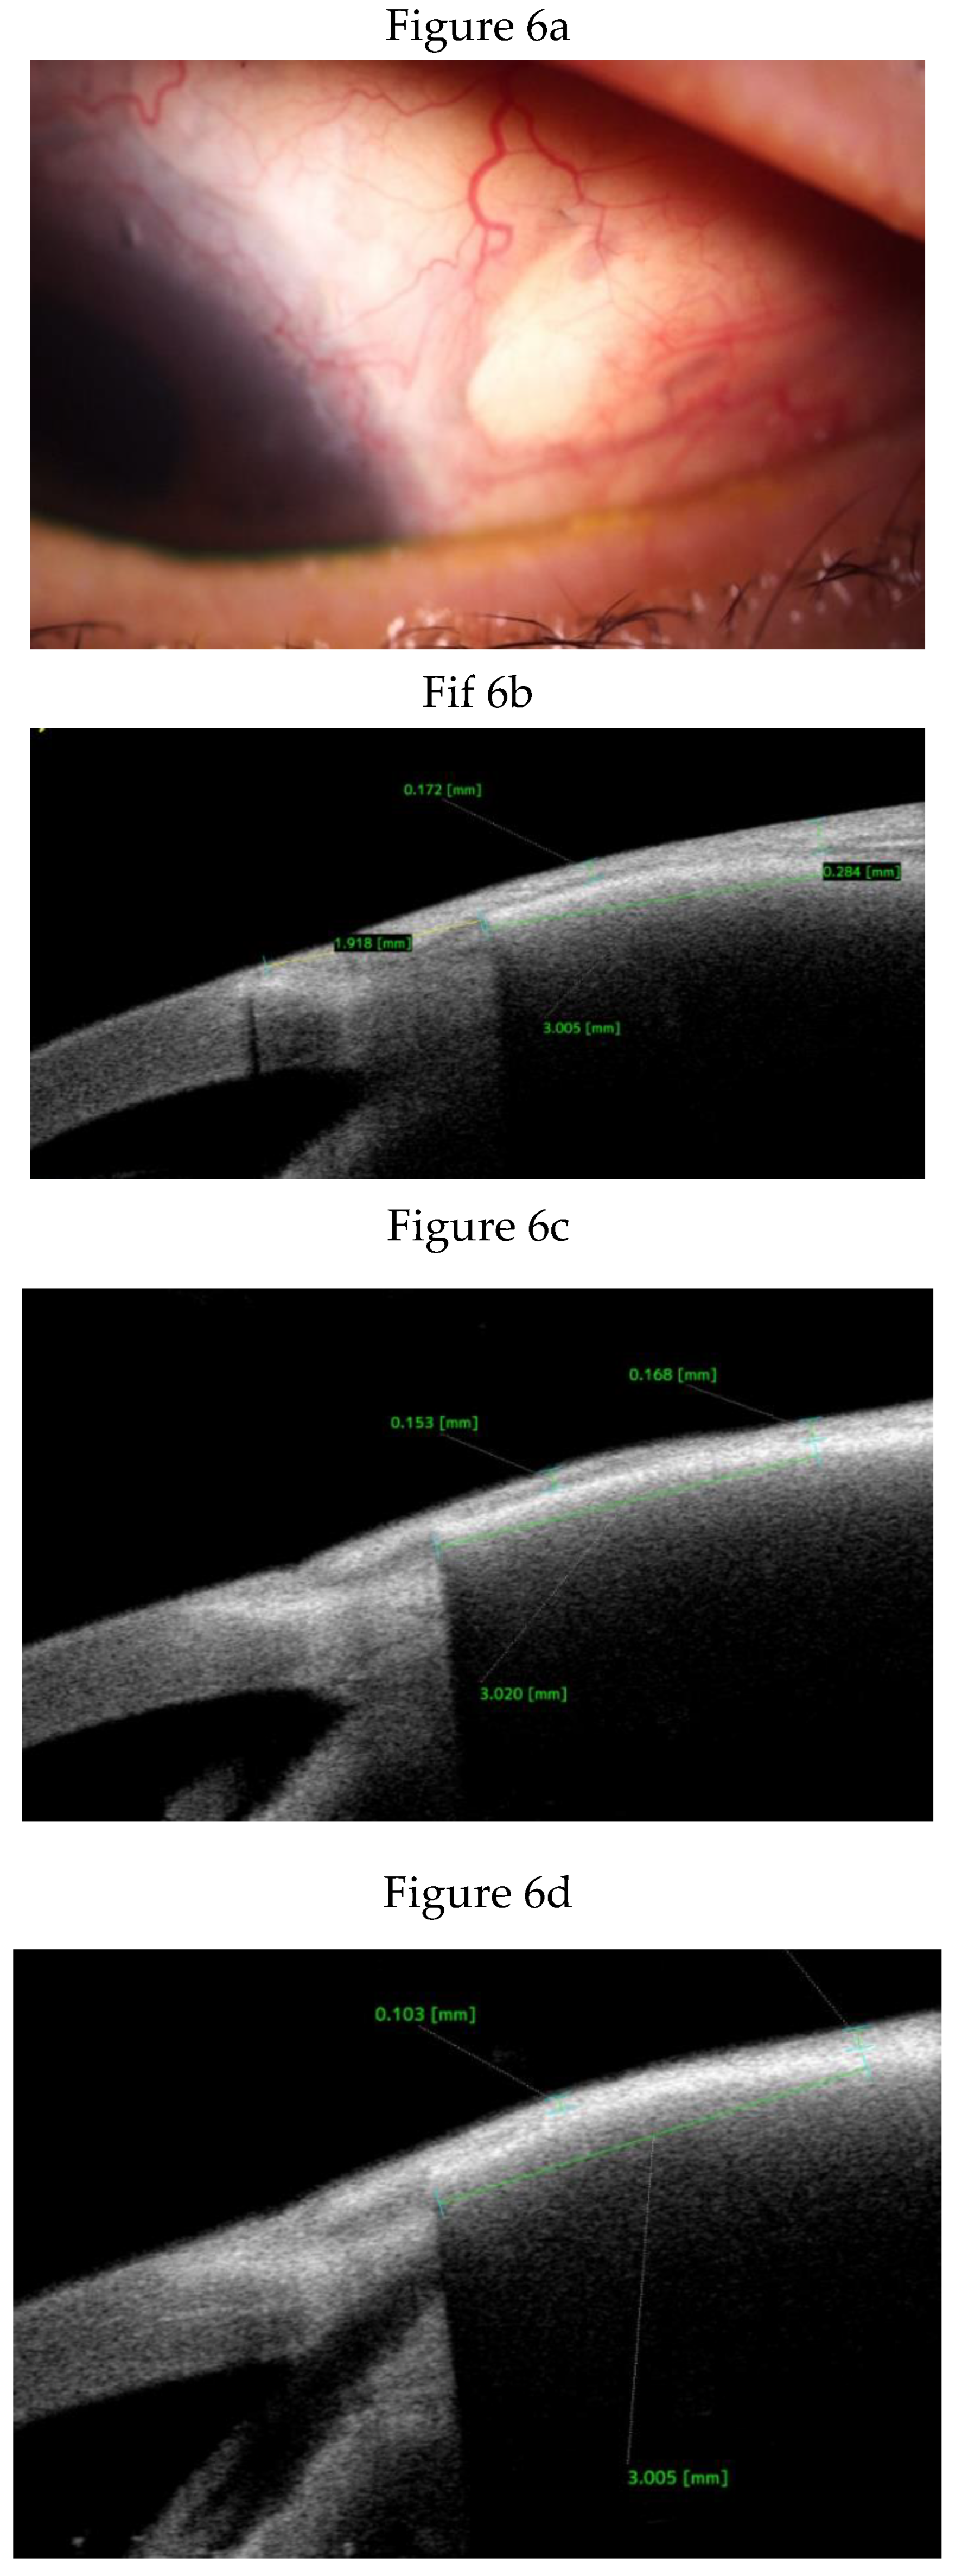

Clinical Course and Conjunctival Thickness in a Representative Case